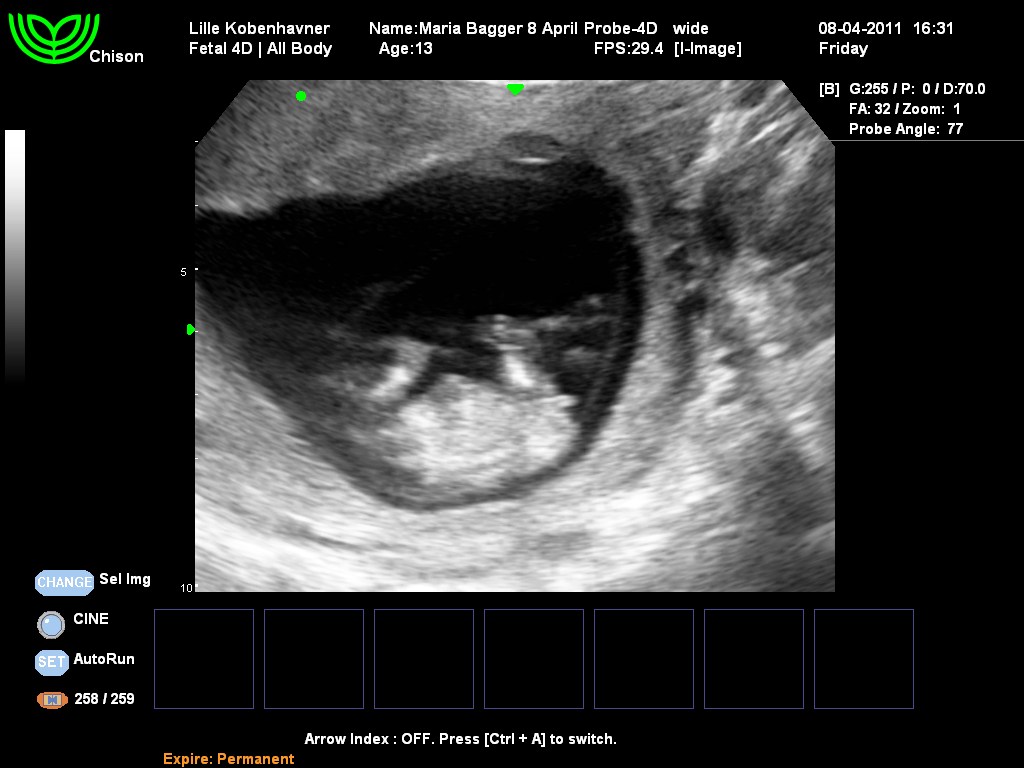

Er 13+1, har lige været til NF idag, og det lille spir målte allerede 6,8 cm... Går godt nok stærkt!

Når men, under scanningen viser jordemoderen mig baby fra "hoved til hale". Af ren nysgerrighed spørger jeg hende om, hvorvidt at man allerede nu kan se kønnet eller ej.

Hun zoomer ind ml. baby's ben, og fortæller os, at hvis det havde været en dreng havde vi højst sansynligt nok allerede nu kunne skimte en lille tap. Så hendes kvalificerede bud lød på: EN PIGE